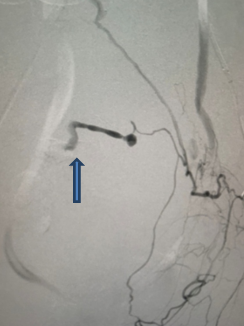

Khoa sản và DSA hội chẩn quyết định nút mạch chọn lọc bằng vật liệu tắc mạch tạm thời. Bằng hệ thống chụp mạch số hóa xóa nền DSA, kíp can thiệp đã định vị đưa dụng cụ đi từ lòng động mạch đùi lên động mạch chậu gốc xuống động mạch chậu trong 2 bên để đi vào động mạch tử cung, nút tắc động mạch tử cung một cách chọn lọc ngăn chặn sự chảy máu.

Chụp DSA chọn lọc động mạch tử cung bên trái thấy hình ảnh chảy máu (mũi tên)

Sau hơn 15 phút làm thủ thuật, bệnh nhân đã được cầm máu hoàn toàn, không còn chảy máu ra âm đạo, huyết áp và mạch trở lại bình thường.